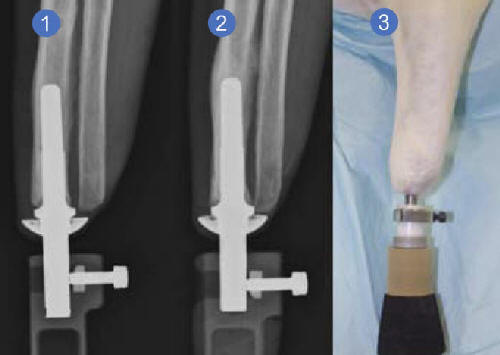

Nažalost, čak i visoko funkcionalnost proteze ne može uvijek pružiti pacijentu mobilnost koju je prije posjedovao. Osim senzacije tuđinski predmet često djeluje kao distrakcija ili čak i odbojni faktor koji ne dopušta opažanje proteza kao potpuna zamjena za izgubljenu ruku ili nogu. By međutim, intraosna tehnologija može to popraviti transkutana amputacijska proteza “(ITAP), podrazumijevajući radikalno drugačiji pristup principima protetike. Zajedničko britanskih naučnika sa Univerziteta u Londonu i Kraljevska nacionalna ortopedska bolnica bila je Dizajniran je model jedinstvene proteze za stopala. Njegovu odlika je odabrana metoda vezivanja. Umesto da stavite veštačku nogu, popravite je amputacija tijela, upotreba ITAP konstrukcije ugrađuje se posebno dizajnirani metalni element kroz kožu i na taj način direktno povezati protezu sa ljudska kost.

Fotografije iz otvorenih izvora Treba odmah napomenuti koje su bile glasne princip upotrebe implantata kao veza između umjetne udove, kosti i meke tkanine uopće nisu nove. Međutim, autori projekta značajno finalizirao je model metalnog implantata za njegovu brzinu prilagođavanje u tijelu. U julu ove godine održan je prvi izbor. ljudi koji će to saznati tokom praktičnih testova prednosti, karakteristike kao i mogući nedostaci predana verzija proteze. Prema dostupnim informacijama, u ovom trenutno već amputirano 20 čelika držači nove veštačke noge. Pogodnost ITAP implantata potvrđuje Mark O’Leary, koji je postao njegov vlasnik još 2008. godine Rekao je da je izgubljen ud vratio se i mogao je potpuno osjetiti. U prilog tome O’Leary je protetskom nogom uspio da osvoji Kilimanjaro i mnoge drugi planinski vrhovi. Budući da je među prvih dvadeset pacijenata, koji će iskusiti savršenije i naprednije u tehničkom Model plana, Mark O’Leary je već u ovoj fazi neobično primijetio prave senzacije dok se krećete. Da biste izbjegli odbijanje organizam stranog materijala, programeri prilikom stvaranja implantat je iskoristio zaštitni znak građevine … rogovi jelen. Ova formacija ima jedinstvenu poroznu strukturu, koje su naučnici uzeli za osnovu. Koncept ideje je tako da se ćelije kože stapaju zajedno s stranim tijelom, prodirući u pore po analogiji, kao što se događa sa jelenovim rogovima. Autor: Tkanine za brtve trebaju popuniti rupe i začepiti formiranje bakterijskih infekcija, a također pomažu pouzdano popraviti strukturu na prirodan način. I pored broja dobrobiti poput odsustva bolne iritacije na mjestu zglobovi konvencionalne proteze i noge zbog trenja, i takođe je na najvišem nivou razradio povratne informacije između ITAP stopalo i čovjek, tehnologija ima svojih nedostataka. By U osnovi, takva proteza podrazumijeva jednokratnu i konačnu ugradnja. Njenog vlasnika jednostavno neće biti moguće samostalno ukloniti građevina.